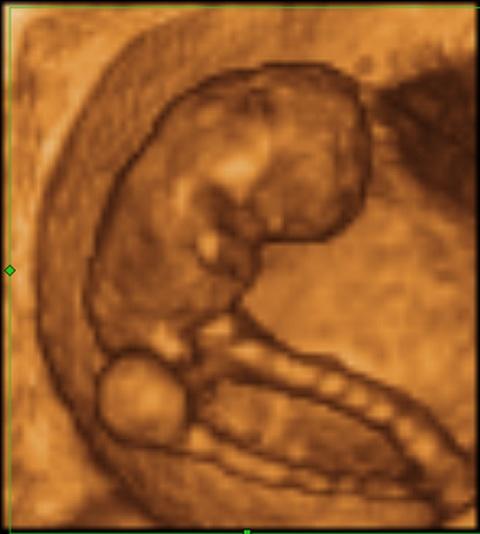

3D ultrazvuk plodu ve stáří 9+2.

V 10. týdnu těhotenství měří plod zhruba 3,1 cm.Při zjišťování délky plodu se měří vzdálenost od temene ke kostrči. Váha plodu je nyní zhruba 4 gramy.

Na konci 10. týdne těhotenství má zárodek všechny zřetelné lidské znaky, od tohoto období mluvíme o plodu.

Lékaři o vašem miminku již nehovoří jako o embryu, ale jako o plodu – začíná fetální období. Děťátko má již zřetelnou lidskou podobu a v jeho těle začínají fungovat první reflexy. Miminko se začíná hýbat, ale vy to ještě necítíte.